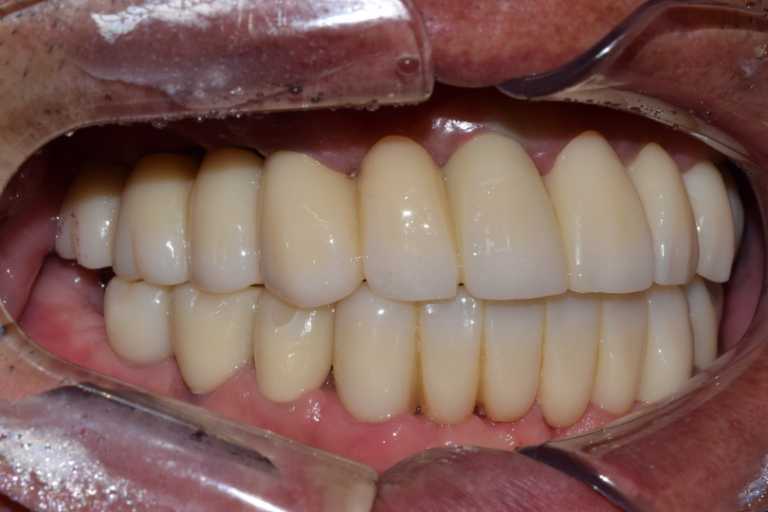

고정형 무치악 임플란트 전후 사례

무치악 임플란트 전후 실제 사례 #1, #2

이미지 위에 가운데 동그라미를 클릭한 상태에서 왼쪽 또는 오른쪽으로 드래그해보세요! 드래그할 때마다 환자의 전후 변화를 확인하실 수 있습니다.

#무치악 임플란트 환자 사례 : 임플란트로 찾은 새로운 미소

#무치악 임플란트 환자 사례 : 기존 치아의 염증 상태로 인해 치료 시작일 때, 잔존치 전체 발치 + 상악동거상술(양쪽) + 뼈이식다수 + 임플란트 픽스처(뿌리) 17개 식립